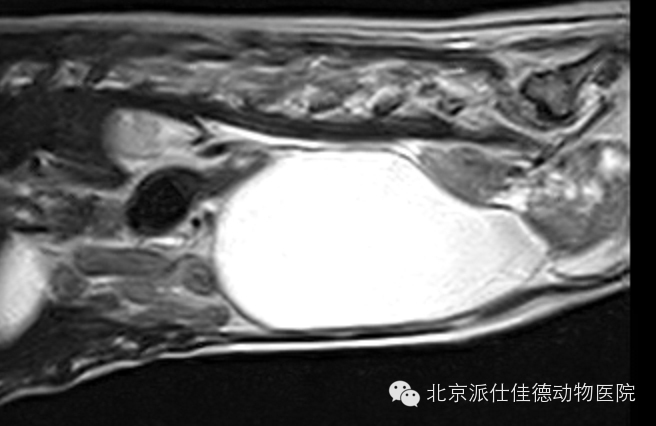

7.有些动物表现腰疼,一直按椎间盘突出治疗,结果经诊断为脊椎肿瘤或是椎管内肿瘤或是脊髓本身肿瘤引发。

15.有些动物表现为转圈,突然四肢共济失调,走路打晃,经诊断发现是脑部肿瘤压迫引发。

16.有些动物表现为突发癫痫,不停的抽搐,经核磁共振扫描发现脑积水、脑炎、脑肿瘤等等。